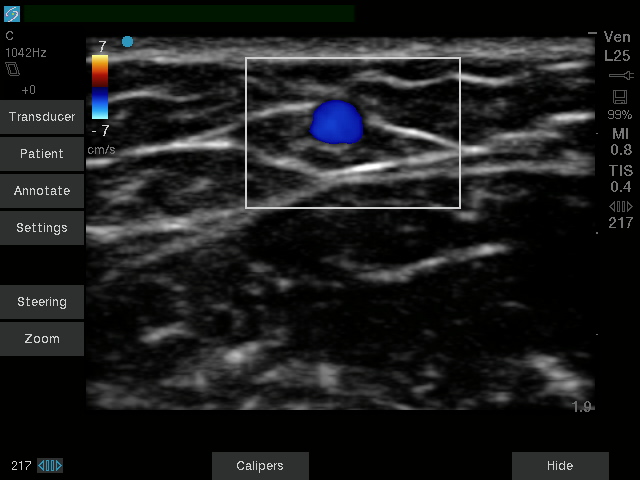

| کاربری | سونوگرافی و اکوکاردیوگرافی |

| کاربری | سونوگرافی و اکوکاردیوگرافی |